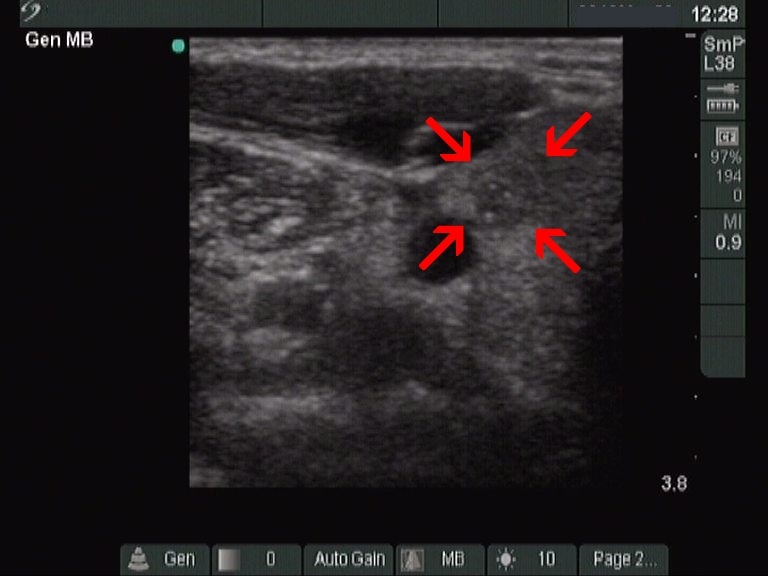

This is an almost completely cystic lesion, however it does not meet the criteria of a pure cyst. The wall thickening (yellow arrows) is ambiguous but there is a tiny solid-appearing area in the dorsal wall (red arrows). In systems which do not use the term 'almost completely cystic lesion', this nodule should be categorized as a peripheral-type cyst.